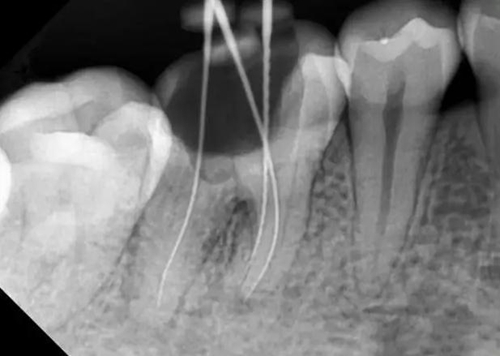

牙根內(nèi)外吸收的原因不同,治療方法和預(yù)后也不一樣。因此,應(yīng)根據(jù)X線(xiàn)和臨床表現(xiàn),區(qū)別內(nèi)外吸收,選擇適應(yīng)的治療方法,用X線(xiàn)根尖片和咬合片的表現(xiàn)區(qū)分牙根內(nèi)外吸收;內(nèi)吸收邊界清楚光滑,形狀多對(duì)稱(chēng),吸收部位根管粗大;外吸收邊界粗糙,密度不一,呈蠶食壯,形狀多不對(duì)稱(chēng),在破壞未穿通根管前,仍能尋找到根管的原始輪廓。偏移投照時(shí),內(nèi)吸收與根管的位置關(guān)系不變,而外吸收部位發(fā)生變化。

內(nèi)吸收是從髓腔或根管內(nèi)壁開(kāi)始,與牙髓炎癥和細(xì)菌感染有關(guān)。一般無(wú)癥狀,多為X線(xiàn)照相時(shí)發(fā)現(xiàn)。應(yīng)盡早行根管治療,去除感染組織后,預(yù)后良好,否則進(jìn)一步發(fā)展會(huì)造成根管壁的穿孔。徹底去除內(nèi)吸收部位的感染組織較為困難,充分沖洗或超聲蕩洗是有效的清潔方法,并在根管內(nèi)封Ca(OH)2蝴劑1周后再根充。由于內(nèi)吸收過(guò)大,根管壁很薄,應(yīng)避免過(guò)大壓力,要選用Ca(OH)2基質(zhì)的蝴劑與牙膠根充,根管壁穿孔較小,可用 Ca(OH)2糊劑根充3個(gè)月,誘導(dǎo)硬組織形成后再根充;或用根管水泥(MTA)根管內(nèi)根充并修補(bǔ)。較大的根管壁穿孔可用MTA從根管內(nèi)或手術(shù)修補(bǔ)。內(nèi)吸收近根尖區(qū)可考慮根尖手術(shù),多根牙可考慮截根術(shù)。

牙根外吸收是從牙周組織開(kāi)始,原因多為創(chuàng)傷,矯正力過(guò)大,埋伏牙,牙齒漂白,再植牙和根尖周炎癥等。因根尖周炎造成的根尖區(qū)外吸收處理方法同內(nèi)吸收,其他因素造成的外吸收采用相應(yīng)的對(duì)因處理和根管治療。